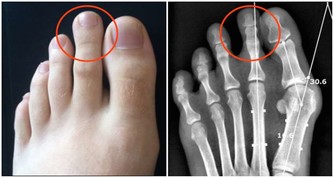

5.海產類

病人不宜多吃海產品,如海帶、海參、海魚、海蝦等,因其中含有尿酸,被人體吸收後,能在關節中形成尿酸鹽結晶,使關節症狀加重。